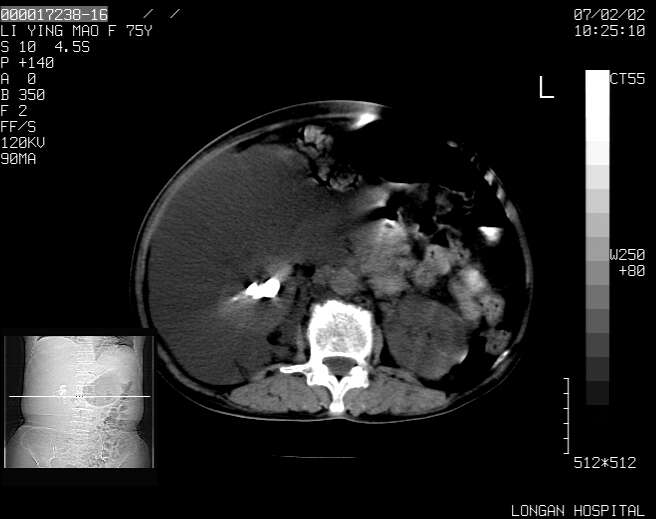

以下是引用dyqct在2007-2-10 8:53:00的发言:[br]考虑:1、肝脏多发囊肿[br] 2、左肾囊肿,右肾多发结石并积水。[br] 3、右胸少量积液。[br] 4、右肾周包裹性积液或淋巴管瘤(有见缝就钻的征象、薄隔、小结节状钙化)?[br] 5、腰椎动脉瘤样骨囊肿?[br] [br] [br]